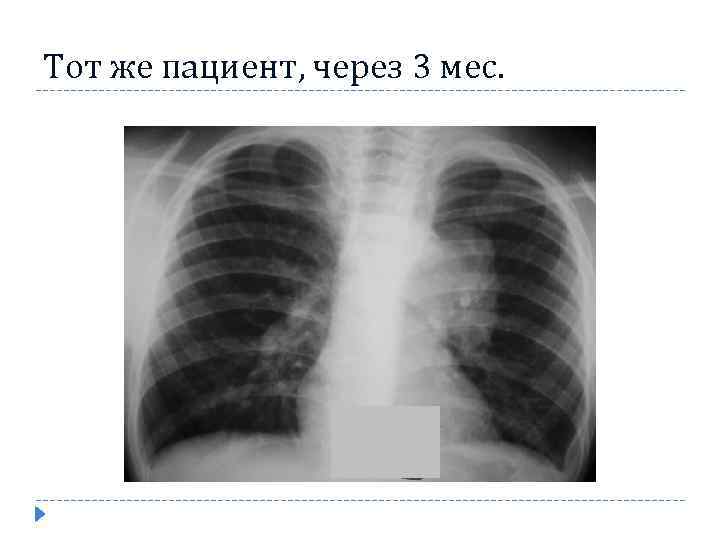

Тот же пациент, через 3 мес.

Тот же пациент, через 3 мес.